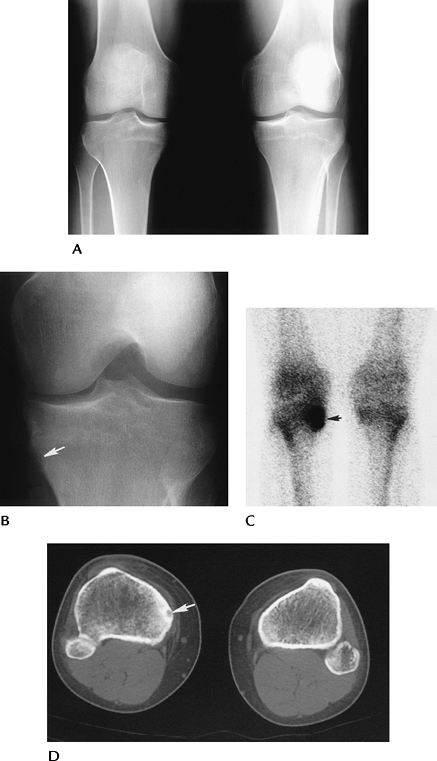

![]() |

FIGURE 5-70 Osteoid osteoma. AP standing (A) and notch (B) views of the right knee showing a questionable tibial defect (arrow). (C) Radionuclide bone scan is positive (arrow) in this region. (D) CT image clearly defines the osteoid osteoma (arrow).